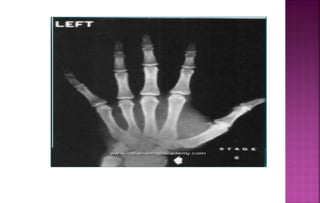

STAGE-I (PP2) (Males 10.6 yrs ,

Females 8.1 yrs)

The epiphysis and diaphysis of proximal

phalanx of Index finger are equal.

It occurs approximately 3 years before the

peak of pubertal growth spurt.

They divided skeletal development in to 9 stages. Each

of these represents a skeletal maturity. Appropriate

chronological age for each of the stages was given by

Schopf in 1976.